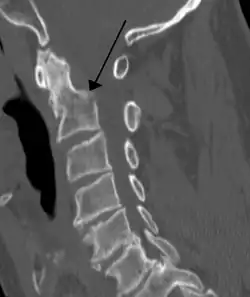

On CT scan or X-ray, a cervical fracture may be directly visualized. In addition, indirect signs of injury by the vertebral column are incongruities of the vertebral lines,[7] and/or increased thickness of the prevertebral space:[8]

![CT scan of normal congruous vertebral lines[7]](./_assets_/Vertebral_lines.png)